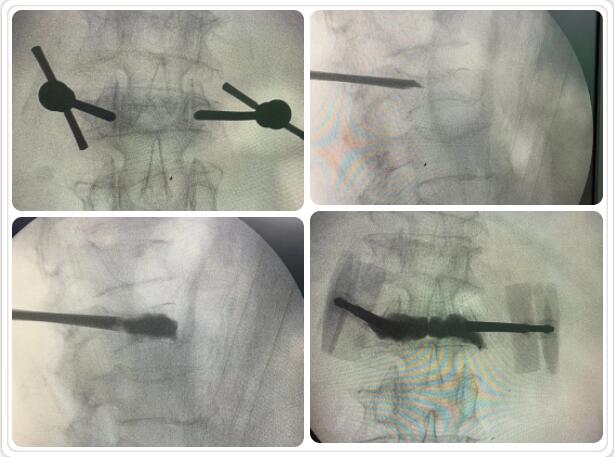

經(jīng)皮椎體球囊擴(kuò)張成形術(shù)是目前臨床治療骨質(zhì)疏松性胸腰椎壓縮骨折的常用方法。椎體成形術(shù)是在局部麻醉和透視下在骨折椎體內(nèi)插入一根或兩根長(zhǎng)針,通過(guò)長(zhǎng)針往椎體內(nèi)注入骨水泥固化骨折部位,維持椎體穩(wěn)定,防止傷椎進(jìn)一步塌陷;同時(shí)骨水泥固化過(guò)程中發(fā)熱導(dǎo)致周圍組織壞死、感覺(jué)神經(jīng)末梢毀壞, 產(chǎn)生良好的鎮(zhèn)痛作用。通常術(shù)后第二天即可在支具或腰圍保護(hù)下下床活動(dòng),大大提高了生活質(zhì)量。該微創(chuàng)手術(shù)具有手術(shù)創(chuàng)傷小、起效迅速、安全性高等特點(diǎn),目前已被廣泛應(yīng)用于臨床。

椎體成型(微創(chuàng)手術(shù))過(guò)程